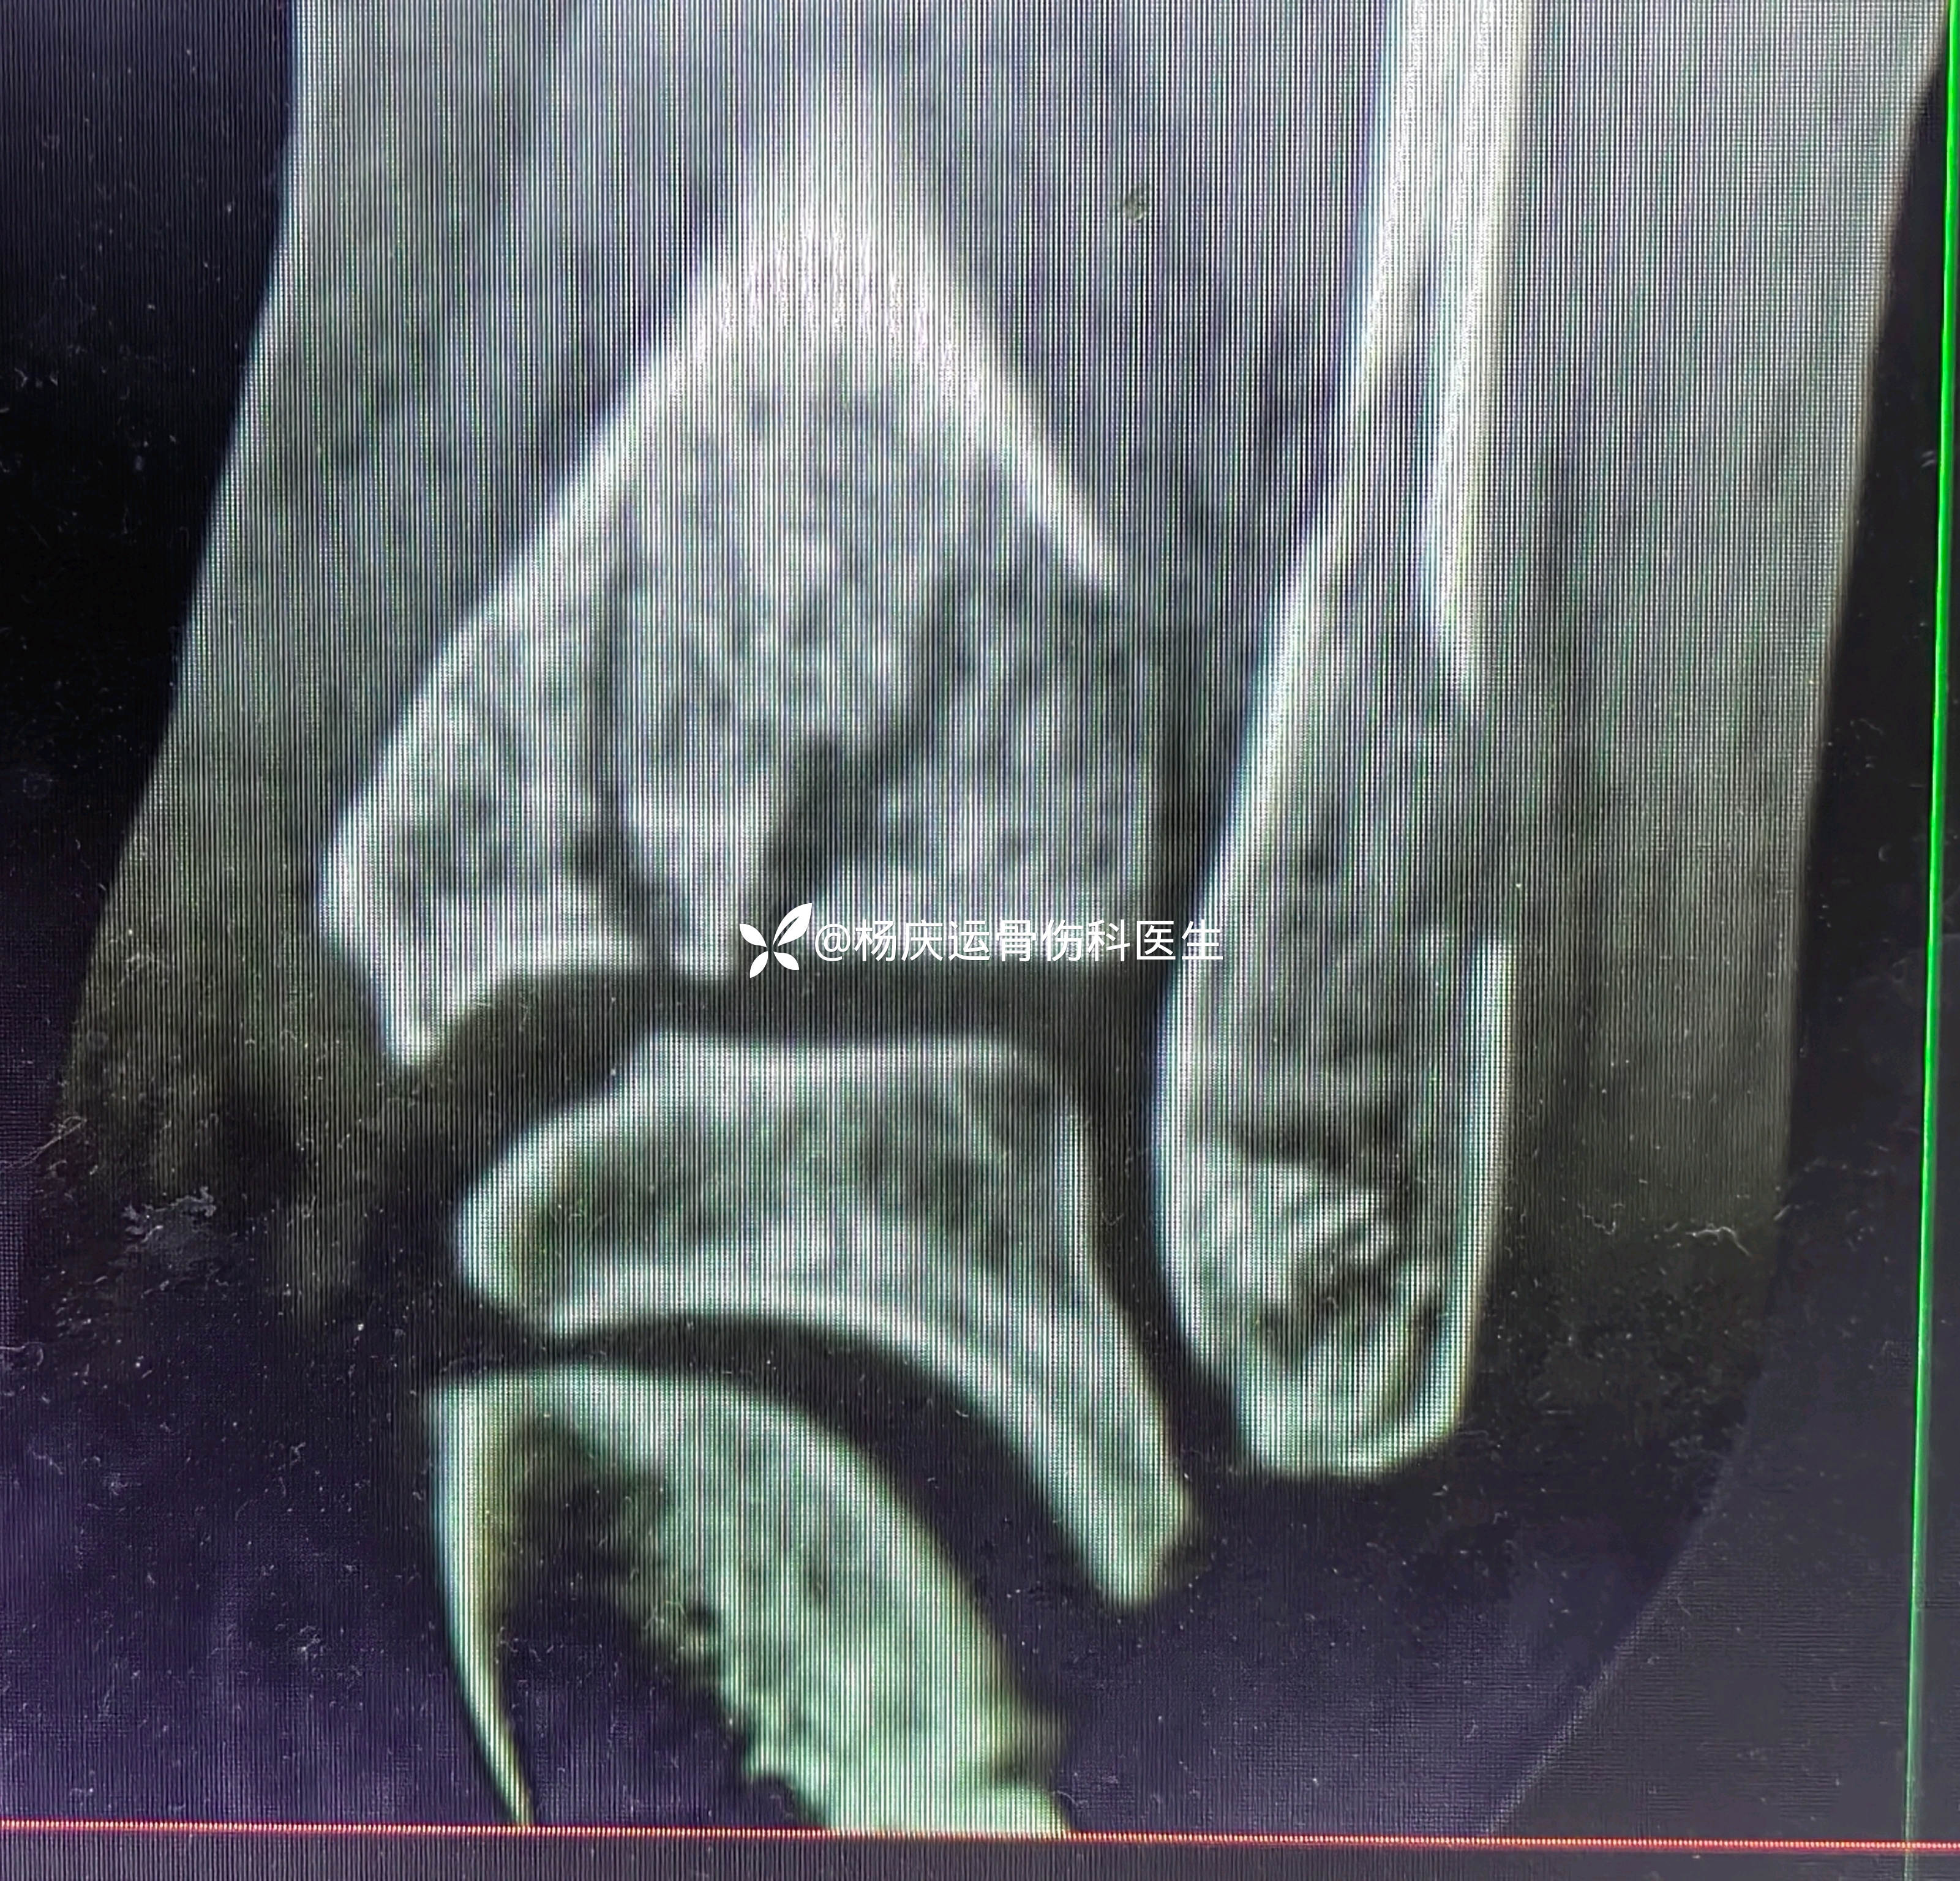

复位后

3天复查CT

关节面台阶约1.0mm